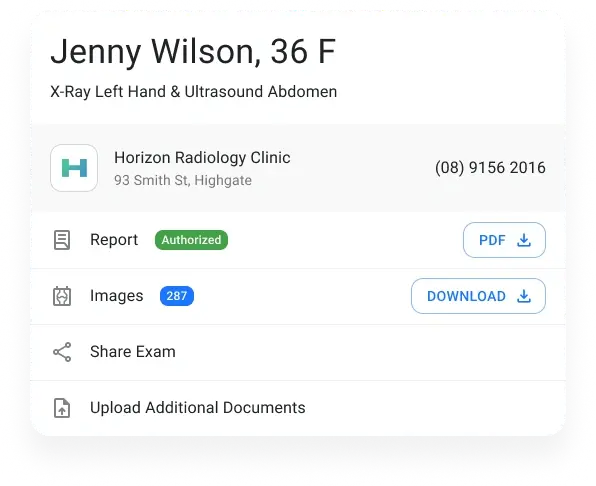

Access Reports

Enable referrers and specialists to access both preliminary and final reports directly through the portal.

DICOM file accessibility

Allow specialists to download complete DICOM files effortlessly, facilitating easy imports into their respective software—ideal for procedures like orthodontics.

Document accessibility

Provide a platform for sharing supplementary documents like growth charts or blood reports, making them readily available on the portal.